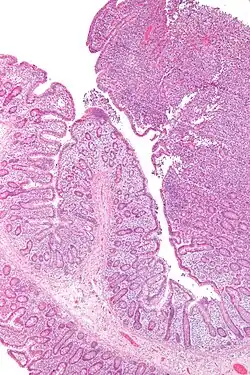

| Micrograph of enteropathy-associated T cell lymphoma (upper right of image). H&E stain. | |